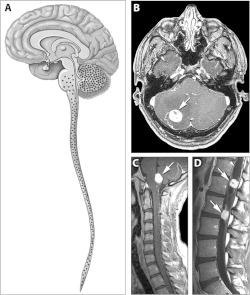

Locations of the main types of cysts and tumors in Von Hippel–Lindau disease.[2] | |